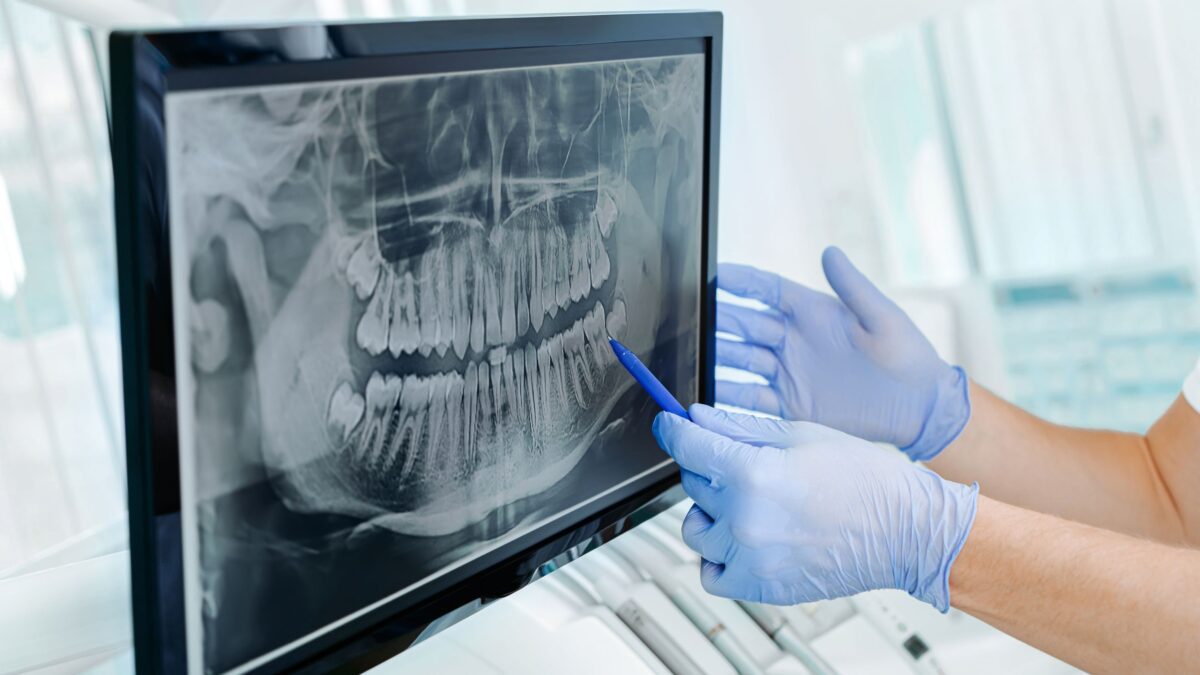

- Review: Once the images are taken, they are displayed instantly on a computer screen. Your dentist will review them with you, explaining any findings and answering your questions. Digital X-rays make it easy to zoom in and highlight specific areas, so you can clearly see what’s happening inside your mouth.